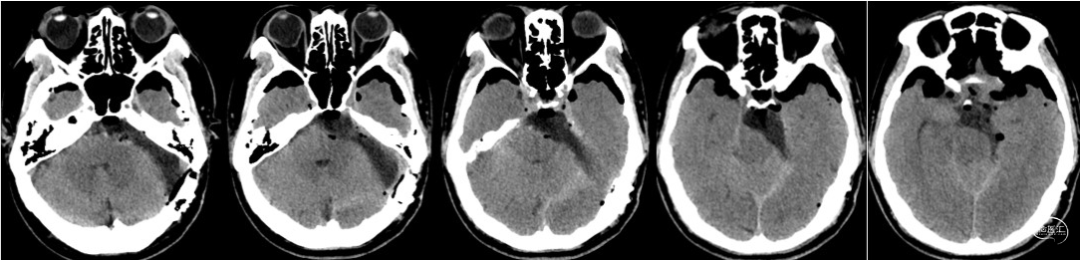

术后CT

患者男性,51岁。 主诉:头晕2月,间断复视1月。 查体:神志清楚,右侧外下方复视。 辅助检查:头颅MRI增强影像诊断:右环池占位,神经鞘瘤可能,请结合临床及MRI平扫原片。 诊断:右侧环池占位,考虑神经鞘瘤。 治疗计划:神经内镜下右侧幕下小脑上外侧入路肿瘤切除术。